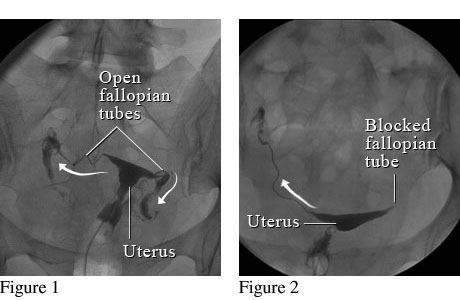

자궁경관에서 자궁강내에 조영제(造影劑)를 주입하고 자궁경관과 자궁강의 크기와 형상, 난관의 소통성, 골반복막의 상황, 유착의 유무, 난소종양의 유무 등을 X-선상(線像)으로 진단하는 방법이다.

⇒ 보통 자궁난관조영술은 자궁 및 난관(나팔관)에 조영제를 사용해서 자궁안쪽에 혹은 없는지 그리고 자궁의 크기나 모양은 괜찮은지 마지막으로 나팔관이 막혀있지는 않은지 등을 조영제를 사용해서 확인하는 방법이다.

그래서 만일 나팔관이 막혀 있지 않다면 자궁안을 채우고 난 이후 나팔관으로 순차적으로 조영제가 빠져 나가는 것이 확인이 되겠지만, 만일 자궁에 혹이 있는 경우엔 그 부분이 검게 뚫어져 있을 것이고, 나팔관이 막혀 있다면 나팔관 바깥쪽으로 조영제가 빠져 나가질 않을 것입니다.

그림1. 정상 나팔관 모습          그림2. 한쪽 나팔관이 막혀 있는 모습